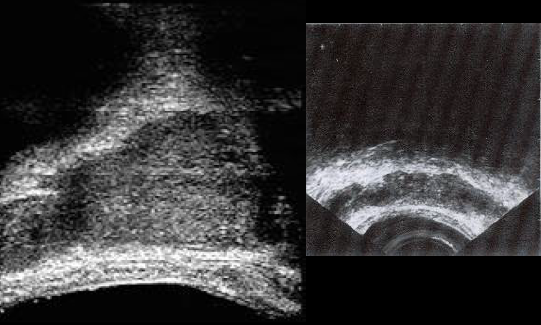

what type of exam is this?

transabdominal, transverse

what plane is this?

saggital

trans

long

what is this showing? how can you tell?verumon

verumontanum. a trans sonogram of the normal prostate. the “eiffel tower” sign (arrowhead) is seen at the level of teh prostatic utricle.

what is this showing?

seminal vesicle